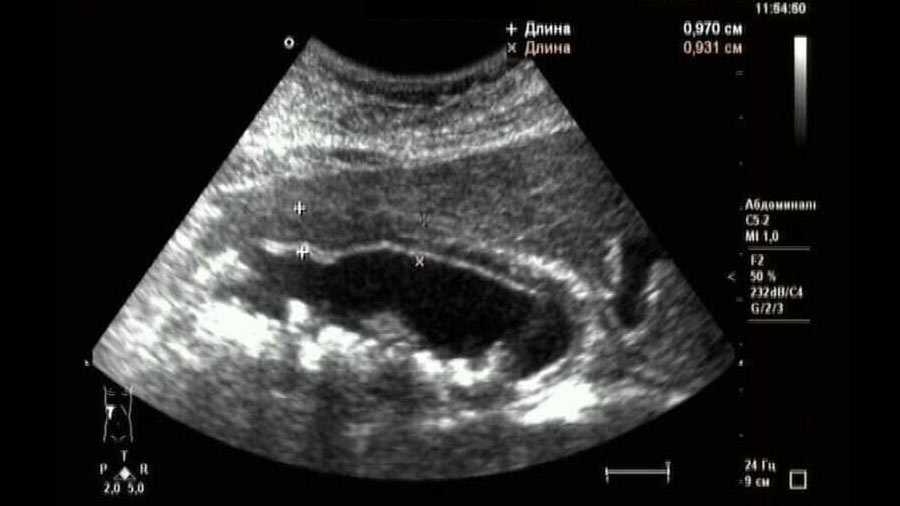

- УЗИ. Обследование позволяет визуально оценить изменения органа. Врач устанавливает форму органа, толщину стенок и его размеры, оценивает сократительную функцию и количество плотных образований при их наличии. На запущенных стадиях при холециститах можно заметить деформацию органа и утолщение стенок.

В этом случае желчный пузырь начинает увеличиваться в размерах, сдавливает сам себя изнутри, стенка его отекает, утолщается, в ней возникает нарушение питания. При ультразвуковом исследовании это хорошо видно: если в норме толщина стенки желчного пузыря 1–3 мм, то в случае воспаления она может увеличиваться до 5–8 мм и более, расслаиваться, становиться более плотной.

Ультразвуковое исследование

Перед проведением УЗИ необходимо удалить шерстный покров с живота – от мечевидного отростка до пупка по 2-3 см с каждой стороны от белой линии. Исследование лучше проводить после 12 часовой голодной диеты, так как пищевые массы и газы будут затруднять изучение. Собаку фиксируют в спинном положении, для этого нужен специальный стол, либо подкладывают скрученные в валик полотенца под бока животного, чтобы ему было удобнее лежатьВ нормальном состоянии желчный пузырь имеет тонкие стенки, которые четко выделяются на фоне содержимого. Но при застое желчи эхогенность субстрата повышается, что ухудшает диагностику – становится трудно отличить от окружающих тканей. Часто наблюдают неоднородный характер желчи в пузыре – гипоэхогенная среда с взвесью различного характера (пылевая, хлопьевидная).

Также обнаруживают изменения в других органах. Часто бывает увеличенным желчный проток – из-за воспалительной реакции стенки утолщены и расширены. В кишечнике находят скопление газов (сильный метеоризм наблюдается в 12-перстной кишке).